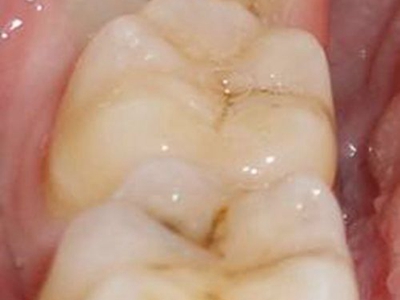

智齿冠周炎牙龈黏膜红肿图

智齿冠周炎患者症状为智齿邻近的牙龈和颊侧黏膜红肿、疼痛,口腔内腺体分泌增加,口水增多。牙齿上面有黑色斑点可发生龋齿,患者可有吞咽时疼痛、口臭等现象。